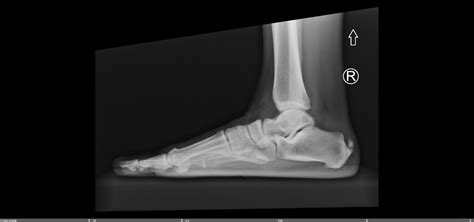

Diagnosing calcification tendonitis involves a combination of physical examination and imaging tests. The diagnostic process typically includes:

• Physical examination: A healthcare provider will assess the range of motion, strength, and tenderness in the affected area.

• Imaging tests: X-rays, ultrasound, or MRI scans can help visualize the calcium deposits and assess the extent of the damage.